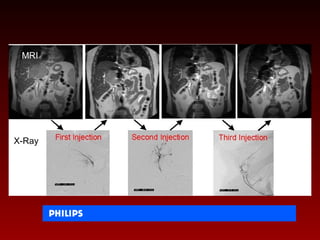

This panel of images shows a sequence of real-time MRI-

guided cardiac injections.

NHLBI - Robert Lederman

This panel ofimages shows a sequence of real-time MRI- guided cardiac injections. NHLBI - Robert Lederman